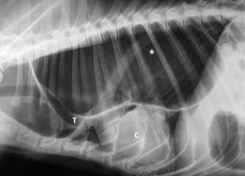

Важно: Мегаэзофагус вызывает именно срыгивание. Если вы видите, что питомец срыгивает непереваренной пищей — это повод для срочной диагностики